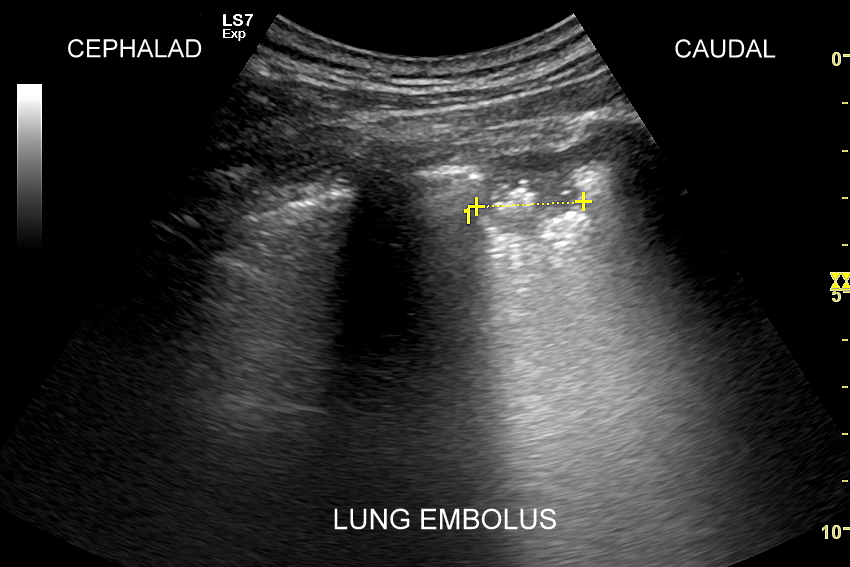

Kluczem do wartościowego zastosowania metody USG w diagnostyce pulmonologicznej jest zrozumienie jej możliwości oraz ograniczeń. USG jest niezwykle czułym badaniem w diagnostyce zapaleń płuc zarówno płatowych, jak i atypowych, np. wywołanych przez Mycoplasma lub Chlamydia. W przypadku zapalenia płuc pojawienie się widocznych zmian sonograficznych wyprzedza wystąpienie fenomenów osłuchowych wykrywanych przy osłuchiwaniu klasycznym stetoskopem. Metoda USG jest również bardzo czuła w diagnostyce chorób opłucnej i jam opłucnowych, takich jak nowotwory opłucnej, odma odma opłucnowa czy płyn w jamie opłucnowej. W rękach doświadczonego lekarza badanie USG może być przydatne w wykryciu zatorowości płucnej, a nawet guzów nowotworowych płuc.

USG płuc | Od tygodnia utrzymywał się u mnie kaszel i ogólne rozbicie, następnie dołączył się ból w okolicy nerki, u podstawy szyi i w klatce piersiowej. Można było pomyśleć, że to przeziębienie oraz kolejna kolka nerkowa. Na szczęście podjąłem decyzję, aby udać się do przychodni, gdzie przyjmował znany mi dr Szczepański. Doktor mnie wysłuchał, osłuchał i wykonał USG. Rozpoznanie zator płucny i skierowanie do szpitala. Zator potwierdzony w tomografii komputerowej i szybko rozpoczęte leczenie. Dlatego żyję! Tomasz S. | Wrocław